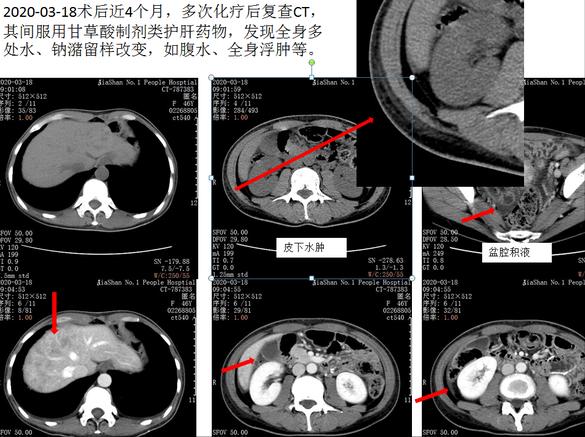

之前就有因为肝功能异常,服用复方甘草酸苷片半月后出现全身浮肿,包括肝周积液、腹腔胸腔等积液等,在排除了低蛋白血症等后,终于锁定元凶并及时更换药物,短期内得到了很好恢复。